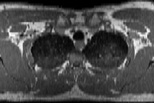

Visible Human male: Sectio transversalis 1333

CT

NMR

Pd T1 T2